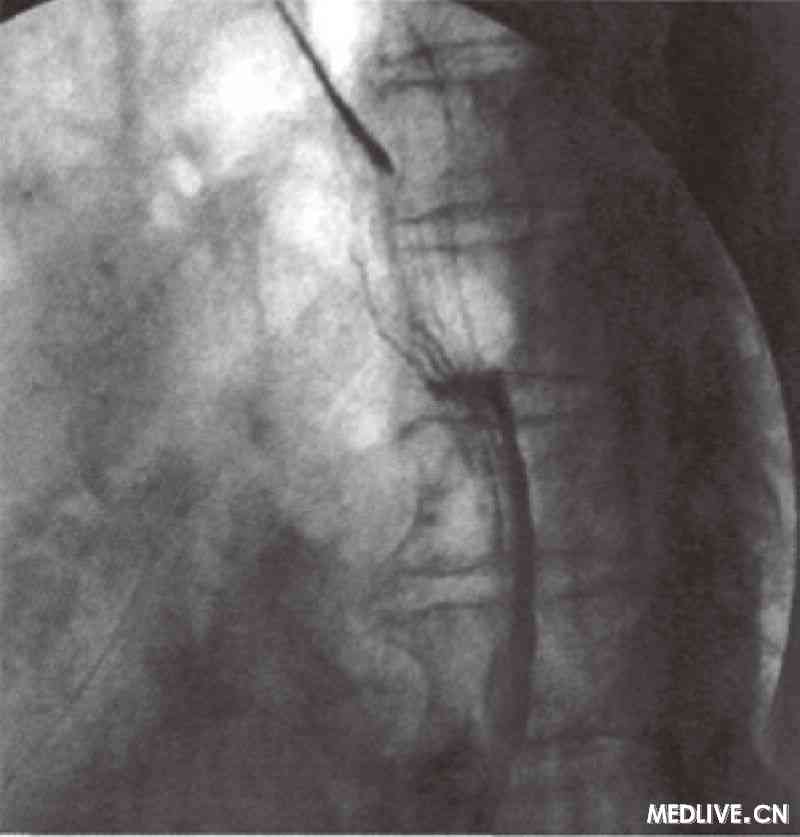

6个月于2010年4月入院。患者6个月前无明显诱因下出现咽下困难,伴胸骨后异物感及梗阻感,呈进行性加重,入院时已不能饮水,但无反酸、烧心,无恶心、呕吐,无上腹痛等。

、高血压病2级。予积极纠正心功能衰竭、抑制心室重塑、控制真性红细胞增多症、抑酸、保护胃黏膜治疗1周,吞咽困难症状得到明显缓解,已能进普通饮食,且较顺畅。